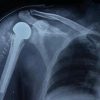

Case illustration 1: Depicted Fig. 2 shows the X-ray image of a patient who presented as type A of AO closed distal tibial fracture and comminuted distal fibula fracture with a tense swelling over ankle. He was managed primarily with open reduction and internal fixation with a plate for the fibula to maintain the length and proceeded with a hybrid external fixator for tibia. He was followed up for fracture union, and the hybrid external fixator was removed at 14-week postoperative period after complete union and ankle mobilization exercise were given. After an intensive physiotherapy session for ankle stiffness, the patient had achieved complete range of movements (Fig. 2). Case illustration 2: Patient presented with open fracture Gustilo Anderson type 3A, AO type C3 proximal tibial fracture with diabetes mellitus. He was operated with wound debridement and hybrid external fixator construct and followed up with serial X-rays, in which union occurred at 16-week postoperative period without any complications (Fig. 3). Case illustration 3: Patient presented with open Gustilo Anderson type 1, type A of AO classification of distal tibial fracture and displaced fibula fracture. He was operated with open reduction and internal fixation with plates for fibula fracture to maintain the leg length then a hybrid external fixator for the distal tibia. Union was achieved at 14-week postoperative period (Fig. 4).